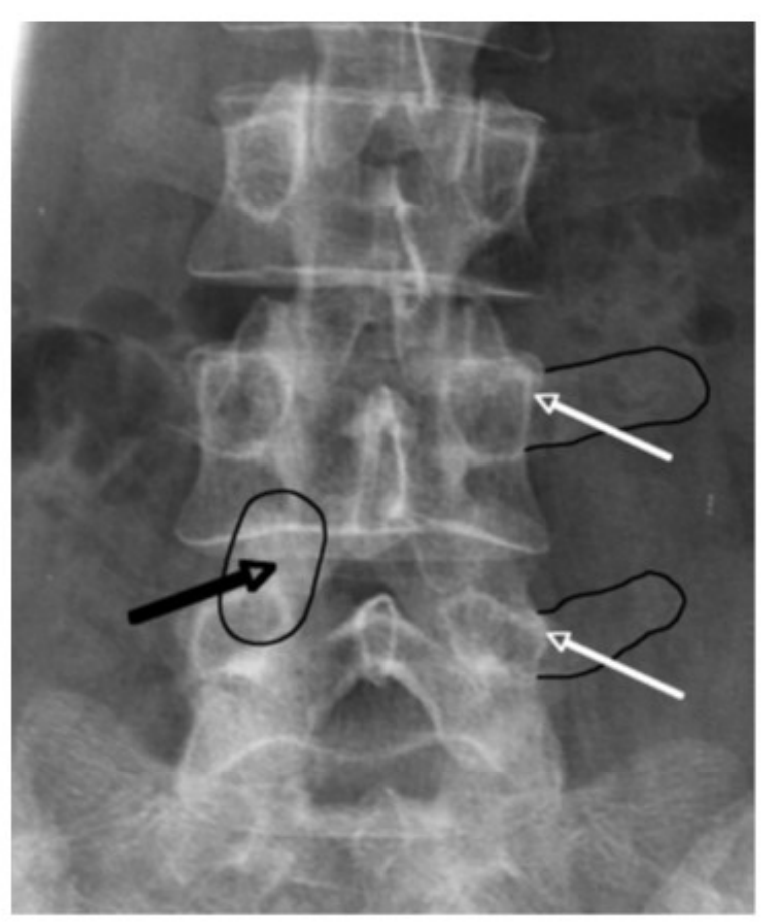

Лечение боли при фасеточном синдроме на поясничном отделе позвоночника

• N=50. Успех 62% через 1 год, лучше результаты у

неоперированных. C.B. Bärlocher, J.K. Krauss, R.W. Seiler. Kryorhizotomy: an alternative technique for lumbar medial branch rhizotomy in lumbar facet syndrome. J Neurosurg (Spine 1) 98:14–20, 2003.

• N=46. Успех 72% через 6 нед и 57% через 1 год. C Birkenmaier, A Veihelmann, H Trouillier et al. Percutaneous cryodenervation of lumbar facet joints: a prospective clinical trial. Int Orthop. 2007 Aug;31(4):525-30.

• N=76. Успех 56% через 1 год. M. Staender, U.Maerz, J.C. Tonn, U. Steude. Computerized tomography-guided kryorhizotomy in 76 patients with lumbar facet joint syndrome. J Neurosurg Spine 3:444 449, 2005.

Методика Bogduk, Dreyfuss

Альтернативная методика (Ambrock и др.)

Какая методика установки криозонда к фасеточным суставам лучше?

• Интенсивность боли после криоанальгезии была меньше, если предварительно проводили блокаду медиальных ветвей по сравнению с перикапсулярной блокадой через 6 недель и 3 месяца (ВАШ 2.2 v4.2, Р .05).

• C. Birkenmaier, A. Veihelmann, H. Trouillier et al. Medial Branch Blocks Versus Pericapsular Blocks in Selecting Patients for Percutaneous Cryodenervation of Lumbar Facet Joints. Regional Anesthesia and Pain Medicine, Vol 32, No 1 (January-February), 2007: pp 27-33